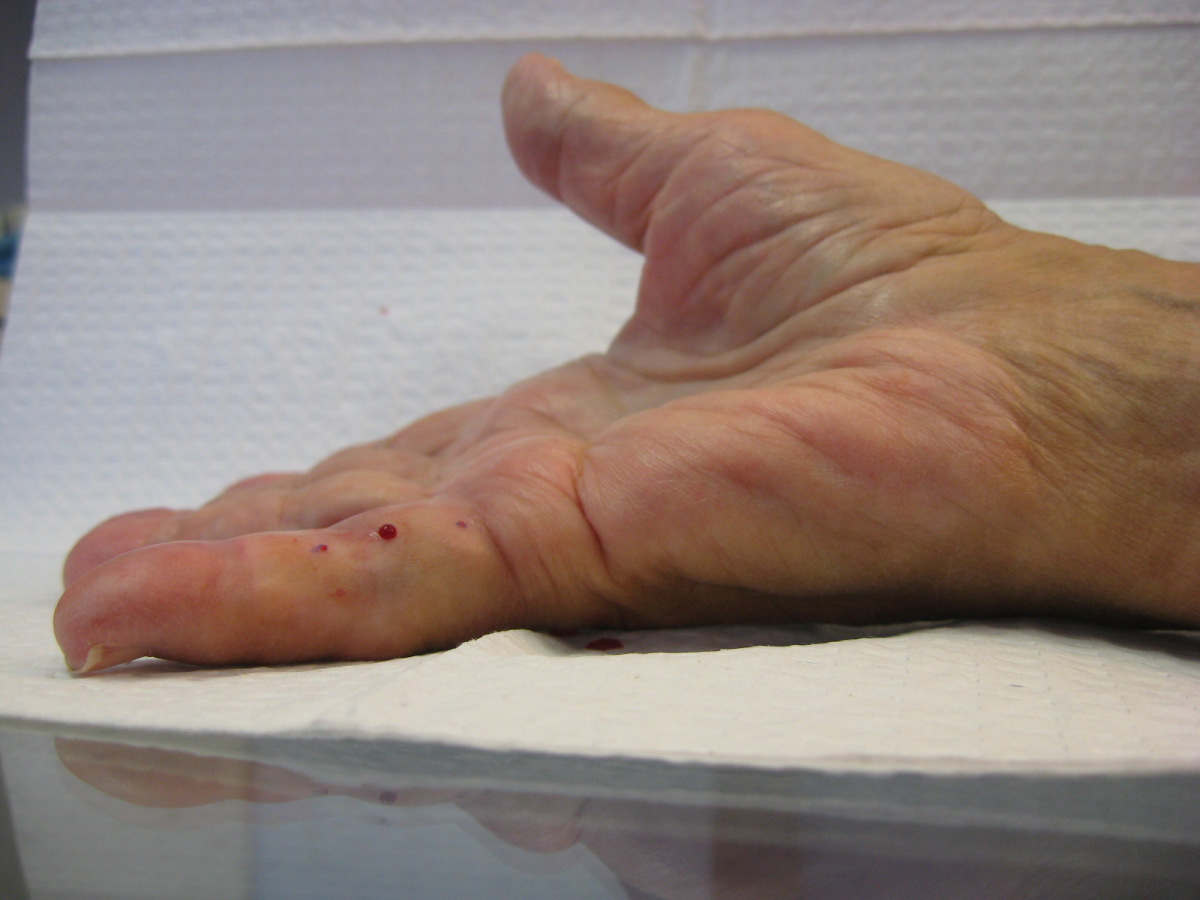

Case 4.

57 year old right handed man with a 22 year

history of Dupuytren disease affecting his

left small finger.

Radiograph of affected finger, 90° contracture.